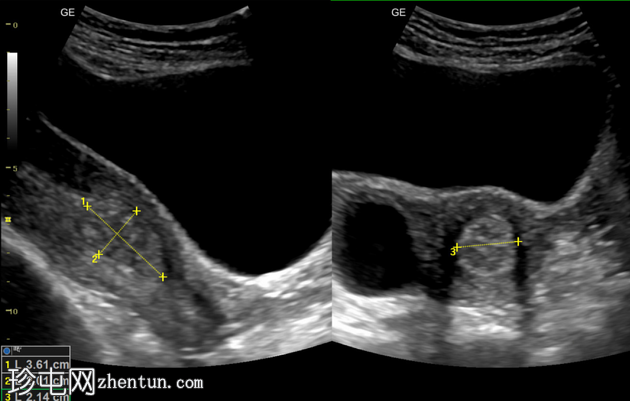

纵切面

横切面

子宫内膜腔内可见边界清晰的高回声病灶,大小为36 x 20 x 21mm,彩色多普勒显示其周围有供血动脉。